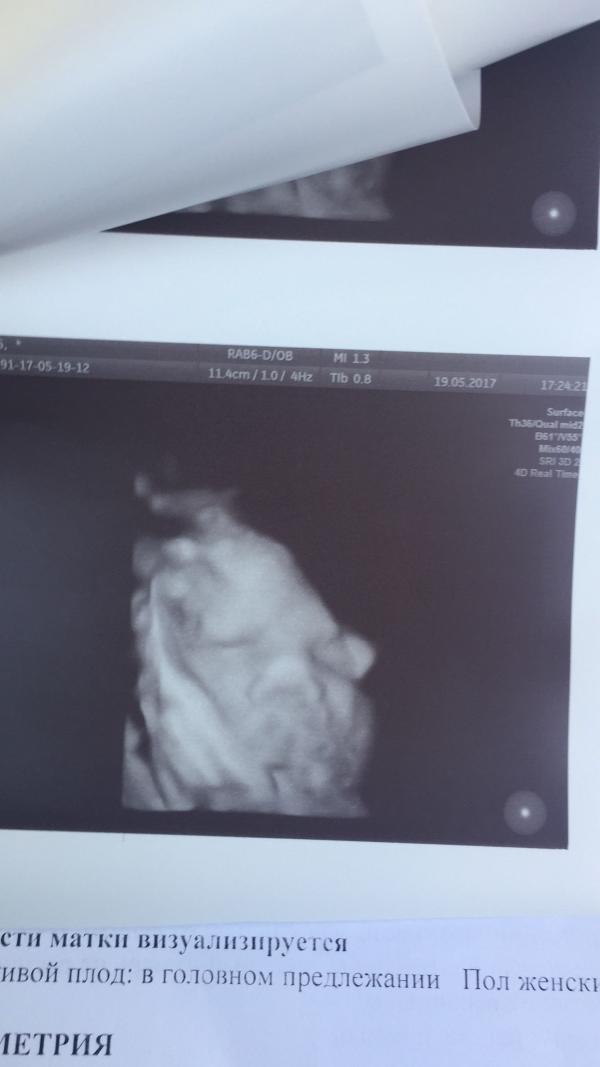

Увидев это УЗИ , подруга сказала моя копия 😱😱😱как это вообще можно понять

😂😂😂😂 3D это жесть конечно) не пойду делать))) а если честно , ну конечно они не такие, очень искажает в зд и4д лучше в обычном сходство искать)) малышка прелесть😍

@sorokinetz, такая же ерунда. Но тут два глазика и нос вижу ) больше ничего